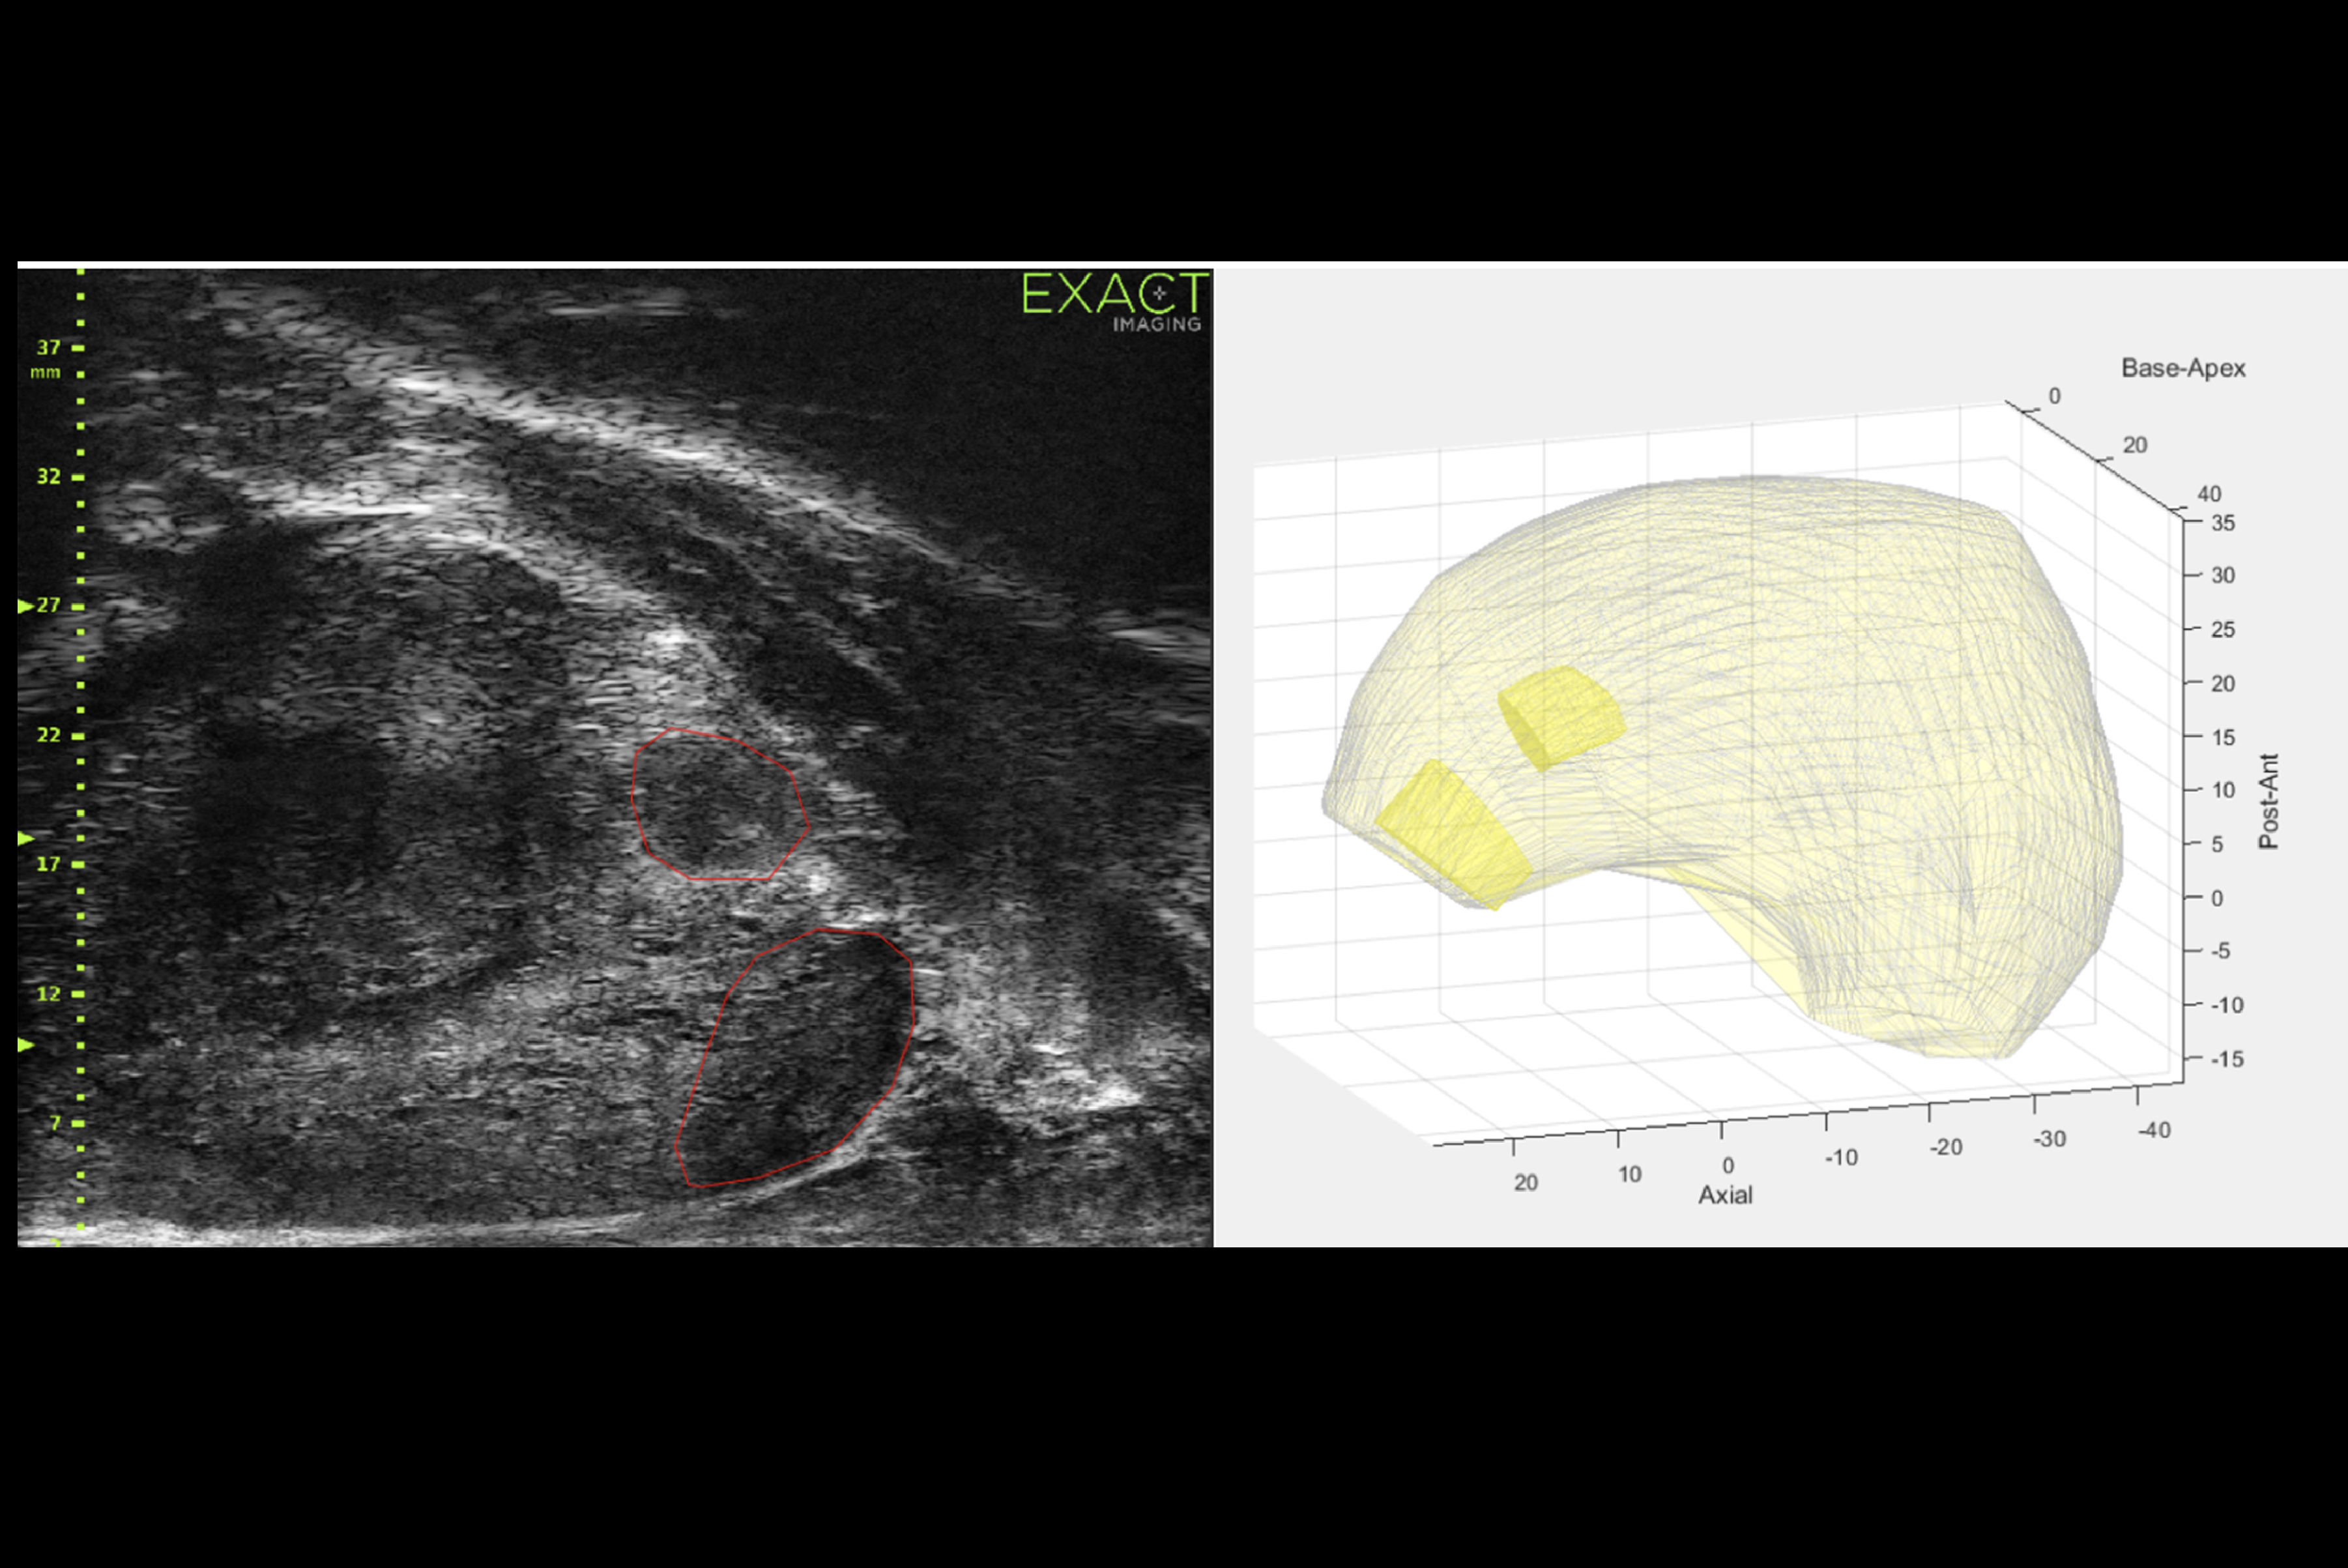

Microultrasound has emerged as an alternative imaging method that uses high-energy sound waves to create images that proponents say are more detailed than conventional ultrasound. It yields an imaging resolution of 70 microns, which is the diameter of a typical prostate duct.

As part of the Optimum randomized clinical trial, Kinnaird and co-authors compared the performance of microultrasound (ExactVu, Exact Imaging) to that of conventional MRI and ultrasound during biopsy for detecting clinically significant prostate cancer. They also investigated whether a combination approach via microultrasound and MRI for fusion-guided biopsy would perform better than that of conventional combined approaches.